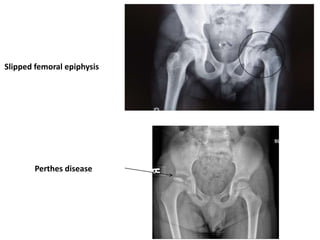

Slipped femoral epiphysis

Perthes disease